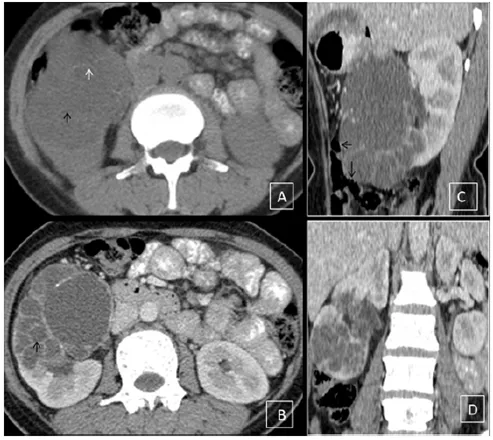

Figure 1: Computed tomography scan of the abdomen (A) Non-contrast axial plane image illustrate a well defined cystic lesion with thin internal septations involving the middle and lower pole of the right kidney (black arrow) with peripherally placed ring-like calcification (white arrow). (B) Post-contrast axial plane images illustrate multiloculated cystic lesions with internal daughter cysts (black arrow). Post-contrast computed abdominal tomography scan (C) Sagittal plane (D) Coronal plane images demonstrate large cyst with a non-enhancing wall (black arrow) and internal septations involving middle and lower pole of the right kidney.

Hydatid disease is a zoonotic disease caused by Echinococcus granulosus or Echinococcus multilocularis.[1] Rudolph, in 1808 first used the term “hydatid” to describe echinococcosis,which in ‘Greek’ means watery vesicle. Definitive hosts of the disease are dogs, foxes, or other canids.[2] Humans are accidental hosts of the disease in whom it can affect almost every system.[3] Urinary tracts are the rarely involved organ in this entity, and secluded renal involvement is rare (2–4% of all cases).[4,5] The patient usually presents with non-specific symptoms like hematuria, vague flank or lower abdominal pain, or it may rupture, leading to hydatiduria. Renal hydatid cysts are classified into five types, (a) Type I cysts are unilocular, without internal architecture, (b) Type II cysts contain focal or diffuse detachment of the inner germinal layer, (c) Type III cysts are multiseptated daughter cysts,(d) Type IV which contain dense folded membranes, internal echoes and has the heterogeneous appearance, and (e) Type V has pericystic ring-like calcification, signifies dead parasite.[6] It can mimic other renal pathologies due to its morphological resemblance; however, the combinations of characteristic imaging findings and serological tests (like hypereosinophilia) usually make the diagnosis.Ultrasonography (US) and computed tomography (CT) are commonly used imaging modalities; however, most of the time, a CT scan is needed to exclude close differentials like a simple cortical cyst, abscess, cystic nephroma. The cyst wall in type I hydatid cyst and the daughter cysts of type II are better delineated with contrast-enhanced CT than sonography. Contrast CT imaging also helps differentiate abscess, as an abscess will show a thick enhancing wall, internal necrosis, thickening of Gerota's fascia, and perirenal fat stranding. The CT scans also help differentiate between Type IV hydatid cysts and tumours, as the CT can easily demonstrate multiple daughter cysts and delineate ring-like calcification along the cyst wall, which signifies a hydatid cyst while avid heterogeneous enhancement in the lesion favours a neoplastic lesion. The CT scan can also assess the other viscera at one go. Surgery is the mainstay treatment for symptomatic renal hydatid cyst through open access or the retroperitoneal approach; however, the retroperitoneal approach is preferred to avoid contamination or spread.[7] A 45 years old female came to our surgery department with a complaint of pain in the right flank region. On physical examination, she had mild fullness in her right lumbar region; however, rigidity/tenderness was present. The routine blood investigations were normal. For further assessment, she underwent a US scan of the abdomen, which demonstrated a complex heteroechoic multicystic lesion in the mid-lower pole of the right kidney. After that, a contrastenhanced computed tomography (CECT) scan of the abdomen was performed, which revealed a thick-walled cystic lesion with multiple daughter cysts. It had ring-like calcifications along the walls of the daughter cysts, and it did not enhance on post-contrast phases.[Figure 1A,1B,1C & 1D] A final diagnosis of renal hydatid cyst was made. The post-operative period was uneventful and patient was on follow up.